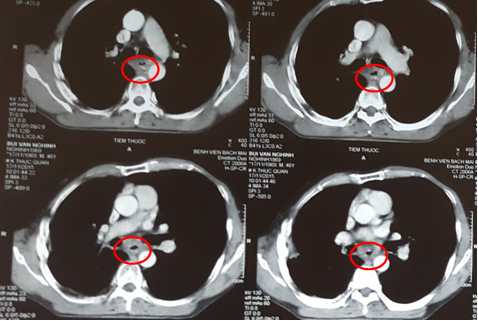

Kết quả chụp cắt lớp vi tính lồng ngực cho thấy: Thực quản đoạn 1/3 giữa dày thành quanh chu vi, không đều, chỗ dày nhất 13 mm, gây hẹp lòng thực quản đoạn dài 50 mm, thâm nhiễm mỡ xung quanh, ôm quanh > ½ chu vi động mạch chủ xuống đoạn ngang mức. Không thấy hình ảnh di căn hạch xung quanh và các cơ quan lân cận.

Hình 2: Hình ảnh khối u thực quản thâm nhiễm mỡ xung quanh (vòng tròn đỏ)